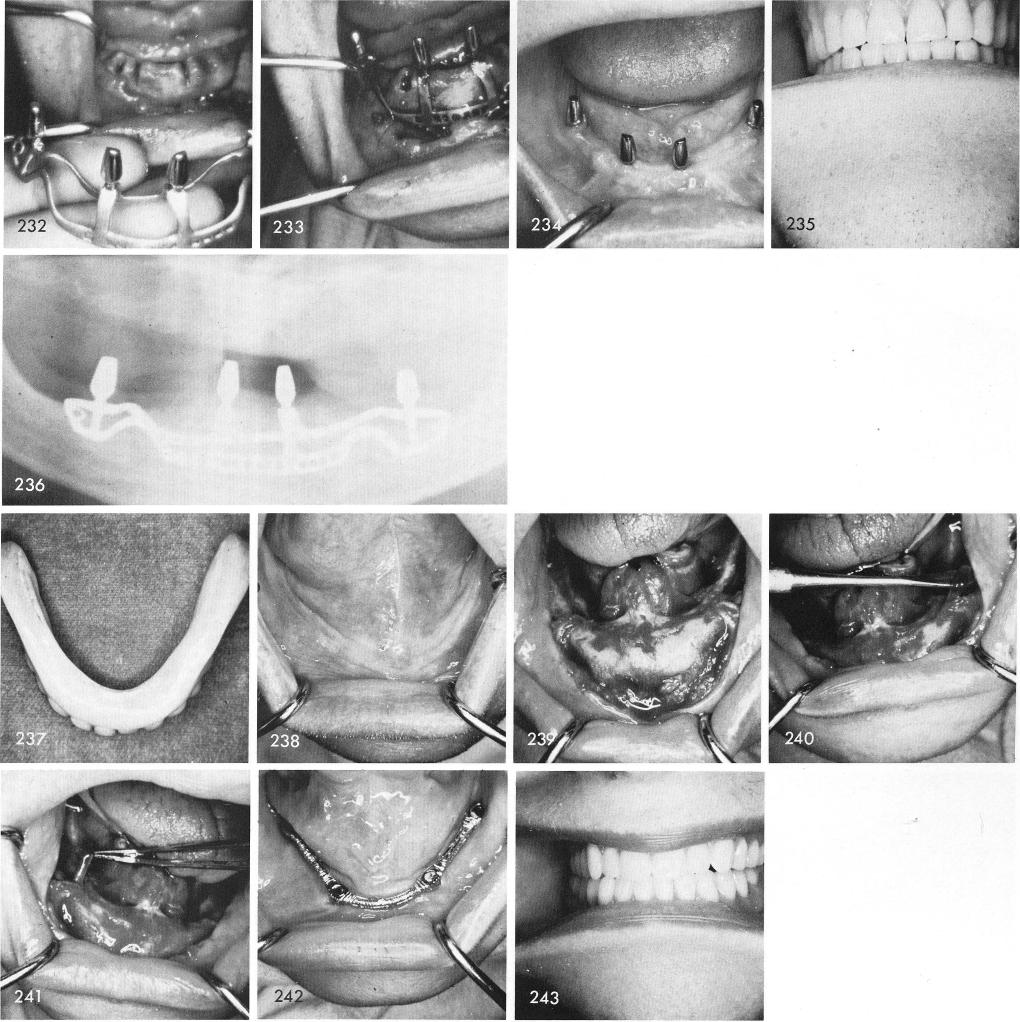

fitted over the bone accurately and the anterior cross-over struts fitted exactly into the grooves, figs. 232, 233. Healing was excellent, fig. 234, and the dentures given to the patient, fig. 235. Fig. 236 is the post-operative x-ray.

A convex tissue bearing denture surface, fig. 237, revealing a concave clinical picture, fig. 238. Enough bone still existed anteriorly, fig. 239, although the inferior alveolar nerve was easily lifted out of its unprotected canal, figs. 240, 241. Healing, here too, was excellent, fig. 242, and the case successful, fig. 243.